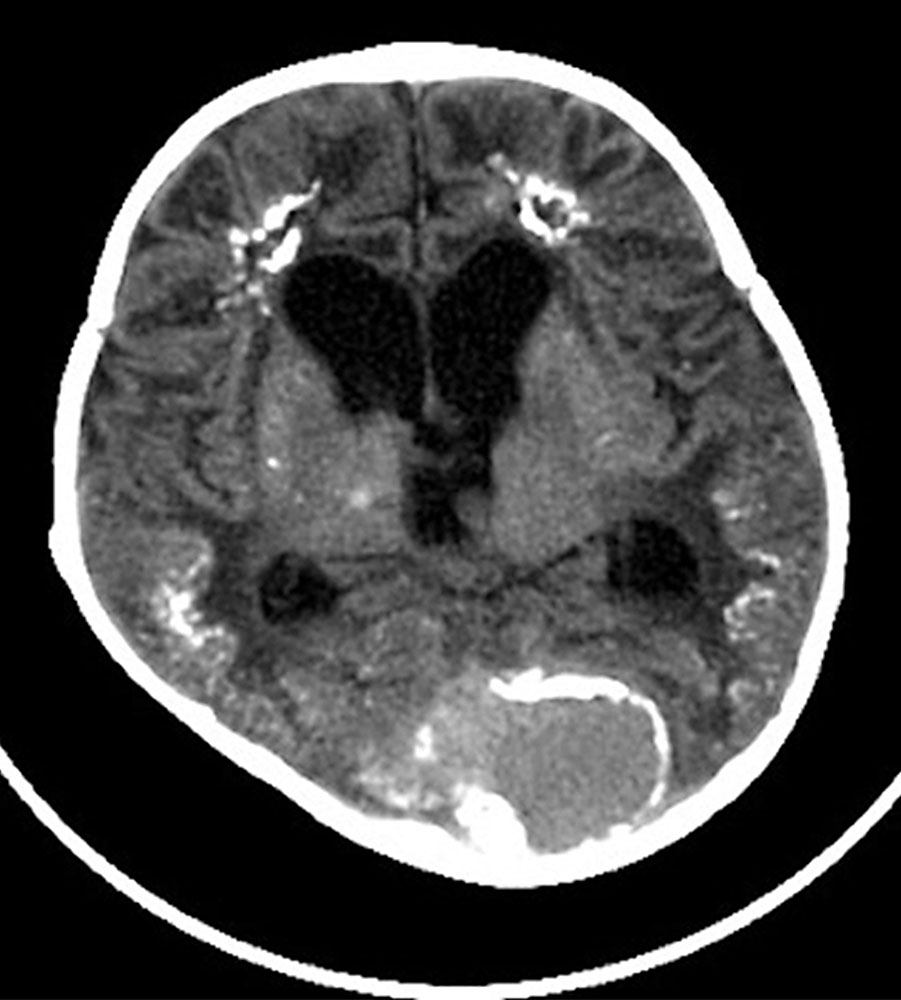

Fetale Fast-flow-arteriovenöse Malformationen (AVM), wie die Vena Galeni Malformation, führen durch erhebliche zerebrale Shuntverbindungen zwischen der Vena magna cerebri und den Arterien aus dem Karotisstromgebiet und dem vertebrobasilären Kreislauf zu einer aneurysmatischen Dilatation der Vena Galeni. Neben zerebralen Komplikationen wie intrakranieller Blutung und Hydrozephalus können betroffene Patienten, abhängig von Ausmaß der Shunts und Alter bei Diagnosestellung, eine Herzinsuffizienz bis zum High-output cardiac failure, pulmonale Hypertonie und Multiorganversagen entwickeln.